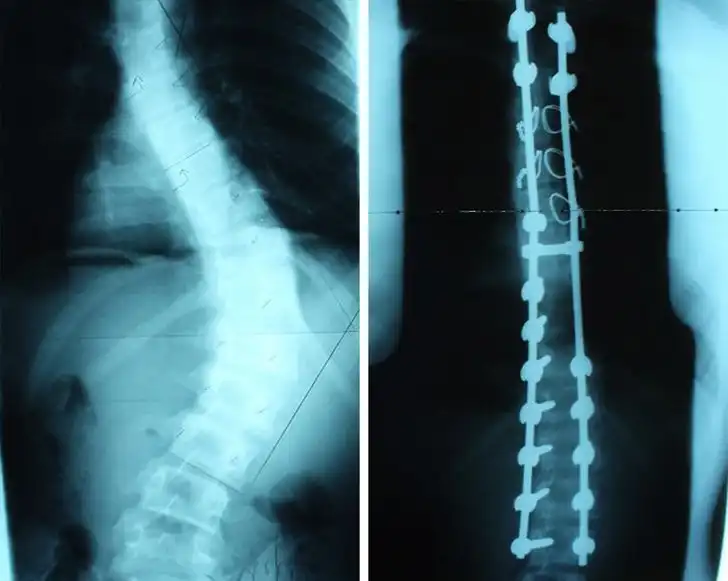

Рентгеновский снимок до и после операции исправлению сколиоза